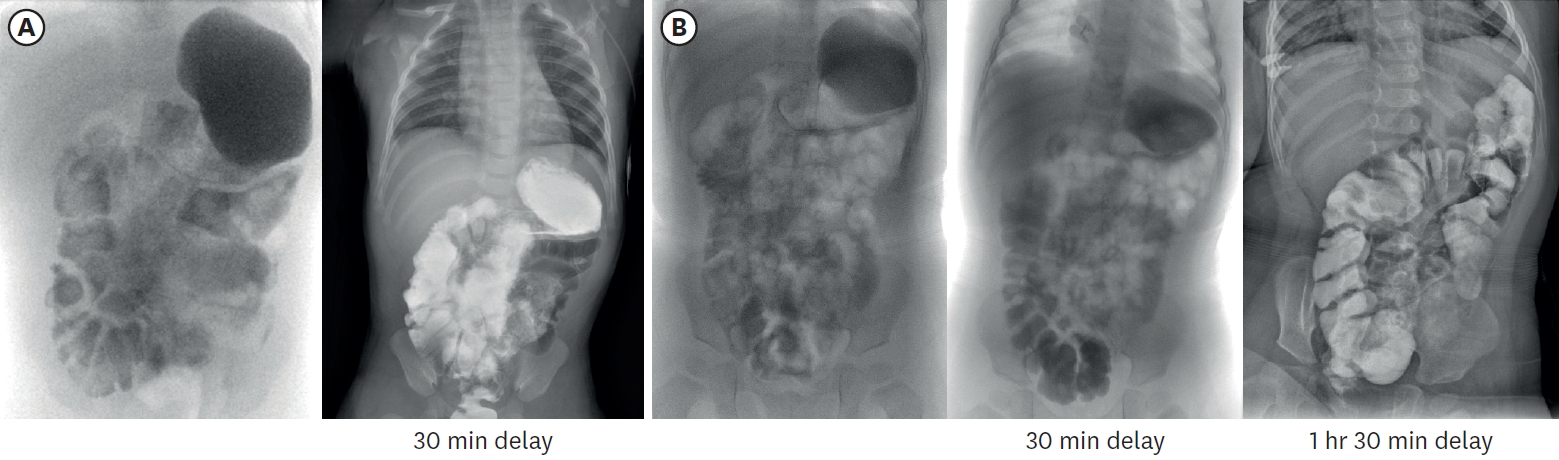

A female infant was born as a twin 1st baby via cesarean section at 35+2 weeks gestation, weighing 2,260 g. Her 38-year-old mother had a history of gestational diabetes, and experienced premature membrane rupture during referral to our hospital. The prenatal ultrasound showed fetal bowel dilatation suggesting small bowel obstruction. Gastric tube drainage was bile-stained, and the abdomen was mildly distended, but not tense. Infantogram showed several distended proximal small bowel loops, with nonvisible rectal gas (Fig. 1A). On the postnatal ultrasound, the rectum and distal sigmoid were all collapsed, with no signs of malrotation or midgut volvulus (Fig. 1B). There was no family history of malformation, and aside from a small atrial septal defect detected on echocardiography, she had no other anomalies.

Fig. 1.

Imaging performed after birth. (A) Infantogram showing multiple dilated loops of small bowel. (B) Following ultrasonography showing dilated proximal small bowel filled with fluid, without definite wall thickening or abnormal vascularity.

Fig. 6.

Small bowel series images taken at 3 months (A) and 16 months (B) of age respectively. In (A), contrast passage to rectum was observed after 30-minute delayed image, and total small bowel length was approximately 23.4 cm, including duodenum. In (B), contrast passage to ascending colon was observed after 30-minute delayed image, and total small bowel length was approximately 29.9 cm.

Stool output was carefully monitored, with diarrhea defined as output exceeding 20 g/kg/d. A notable increase in stool occurred primarily around month 4, when she started increasing enteral feeding, and during the beginning of weaning food. Initially, we adjusted to reduce the amount of feeding and increase TPN fluids to maintain hydration and nutritional supply. After starting weaning food, we tried to modify the ingredients and used various lactobacilli supplements with intermittent antidiarrheal drugs (Racecadotri, Hidrasec® Abbott Korrea, Seoul, Korea). She is currently maintaining a stable stool condition with a normal pattern, averaging 2 times per day and around 6 g/kg (Fig. 3). Through 20 months of follow-up, the patient demonstrated uncomplicated growth, so we gradually extended the outpatient visits and laboratory monitoring intervals from monthly to bimonthly. Last laboratory results taken at 20 months of age were all found to be normal, including liver function, albumin, heavy metals, and vitamins (Table 1). To monitor the bowel’s adaptation process, small bowel series examination was undertaken at 3 months and 16 months of age respectively (Fig. 6). It was noted that the IC valve transit time was increased more than twofold from 7 minutes to 14 minutes. This indicated an enhanced intestinal nutritional retention time, which resulted in improved nutrient absorption and overall intestinal function.